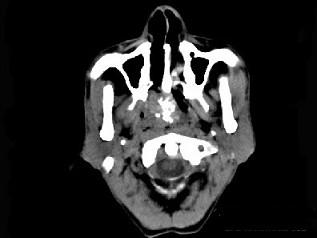

问题 男性,57岁,睡觉打鼾,近来加重,CT扫描如图所示,请选择正确的描述和答案 ( )

选项 A、考虑为鼻咽癌 B、考虑为鼻咽部多形性腺瘤 C、肿块内密度尚均匀,其上方见较多钙化影 D、肿块边缘大部清楚,邻近结构未见明显受侵 E、鼻咽腔偏右侧可见类圆形软组织块影

答案 BCDE